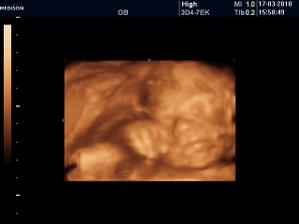

Vyrobene z velkej lasky